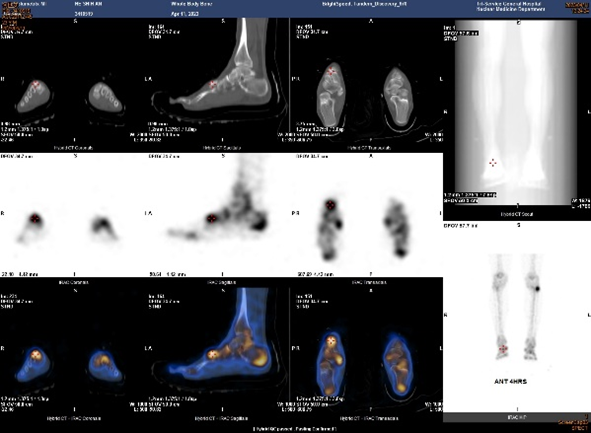

A 23-year-old soldier visit Outpatient Department of Rehabilitation of our hospital for the pain in the bottom of his feet. The patient said that once he exercised the feet hurt a lot, and the pain would relieve after rest. He has been troubled by such a situation since high school. Recently, the situation worsened due to intense training in military service. He mentioned that he had been suffering from chronic knee pain for a long time. The knees were burning and looked reddish, causing pain after exercise even now can be felt heat around knee. During physical examination, we found pustulosis on both palms (Figure 1A & 1B) and hyperostosis in the left sternoclavicular joint. Furthermore, the patient also had a little acne on his face. Plain films of the knee and foot/ankle joints did not show abnormality (Figure 2A). Whole body bone scan (WBBS) divulged a boosted uptake of 99mTc-methylene diphosphonate (99mTc-MDP) at the left knee and both foot/ankle joints (Figure 3). Single photon Emission Computed Tomography (SPECT) with Computed Tomography (CT), using the same tracer, revealed precise pathology at the left knee and both foot/ankle joints (Figure 4A & 4B). The initial impression for this patient was SAPHO syndrome together with enthesopathy of left knee, and both foot/ankle joints. Patient was treated with pain killer and rehabilitation modalities, and his painful episodes improved after three months.

Figure 4A The enhancements of the hybrid SPECT-CT at the left knee confirmed the lesions, in favor of an accompanying sign of SAPHO syndrome.

Figure 4B In the hybrid images of SPECT-CT, the enhancements of uptake exist indicating the evidence of an accompanying sign of SAPHO syndrome.

This case report is the only one that confirms the uptake on the SPECT-CT of the knees and feet in a case of SAPHO syndrome. In this case, we noticed the enhancement of the knee and foot confirmed from SPECT-CT images. Based on the skeletal scintigraphy, despite of the enhancement on bilateral the sternoclavicular joints, the involvement of both knees (especially the left side), and both feet/ankle joints (also especially the left one) was confirmed. These kinds of signs in knee and foot/ankle joints are out of features of SAPHO syndrome. As for the SPECT-CT scan, this might be the first case using SPECT/CT to scan the knees and the feet of a person with SAPHO syndrome.2,3,5,6 As shown on the SPECT/CT, hyperostosis appears on the left knee in the axial view and lesions on bilateral knees (left >> right) in the coronal view. For the feet, we can find large area enhancement covering them.